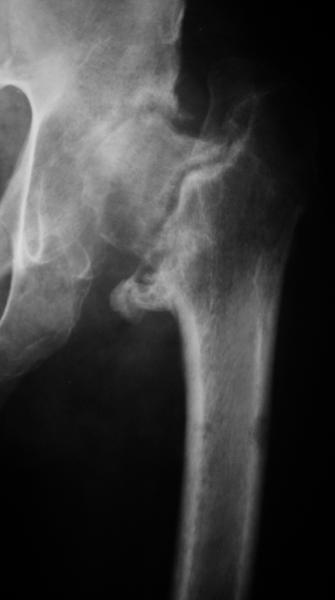

Еще пара фото, ситуация несколько иная, задачи те же, открытое вправление застарелого вывиха в 2002, молодой возраст. Сейчас госпитализирована для эндопротезирования.

А за счет чего такое укорочение? По снимку не видно соответствующего дефекта. Ну плюс приводящая контрактура - но все равно как-то уж больно много. Может, сделать снимки и таза обзорный с обоими проксимальными отделами бедра, и коенный суставов с приложенной линейкой какой?

Судя по снимку, максимум истинное укорочение около 4 см, что может быть коррегировано интраоперационно. Вопрос в другом: куда ставить ацетабулярный компонент в истинную или во вновь сформированную ( впадина диспластичная).

По рентгенограммам укорочение не более 4 см, остальное возможно за счет контрактуры. Опыта с низведением аппаратом Илизарова нет, но мы одномоментно такие укорочения корригировали вполне успешно (в год 5-10 именно таких и проходит). Лишние этапы пожалуй только будут способствовать инфекции. Доступ чаше применяем передне-наружный, а вот протез наверное поставили бы здесь на цементе - остеопороз выражен.

Ортопедическое укорочение пострадавшей ноги может быть и 7, и 10 см. за счет контрактур в тазобедренном суставе, а вот истинное укорочение, судя по представленным рентгенограммам, вряд ли больше 4 см.